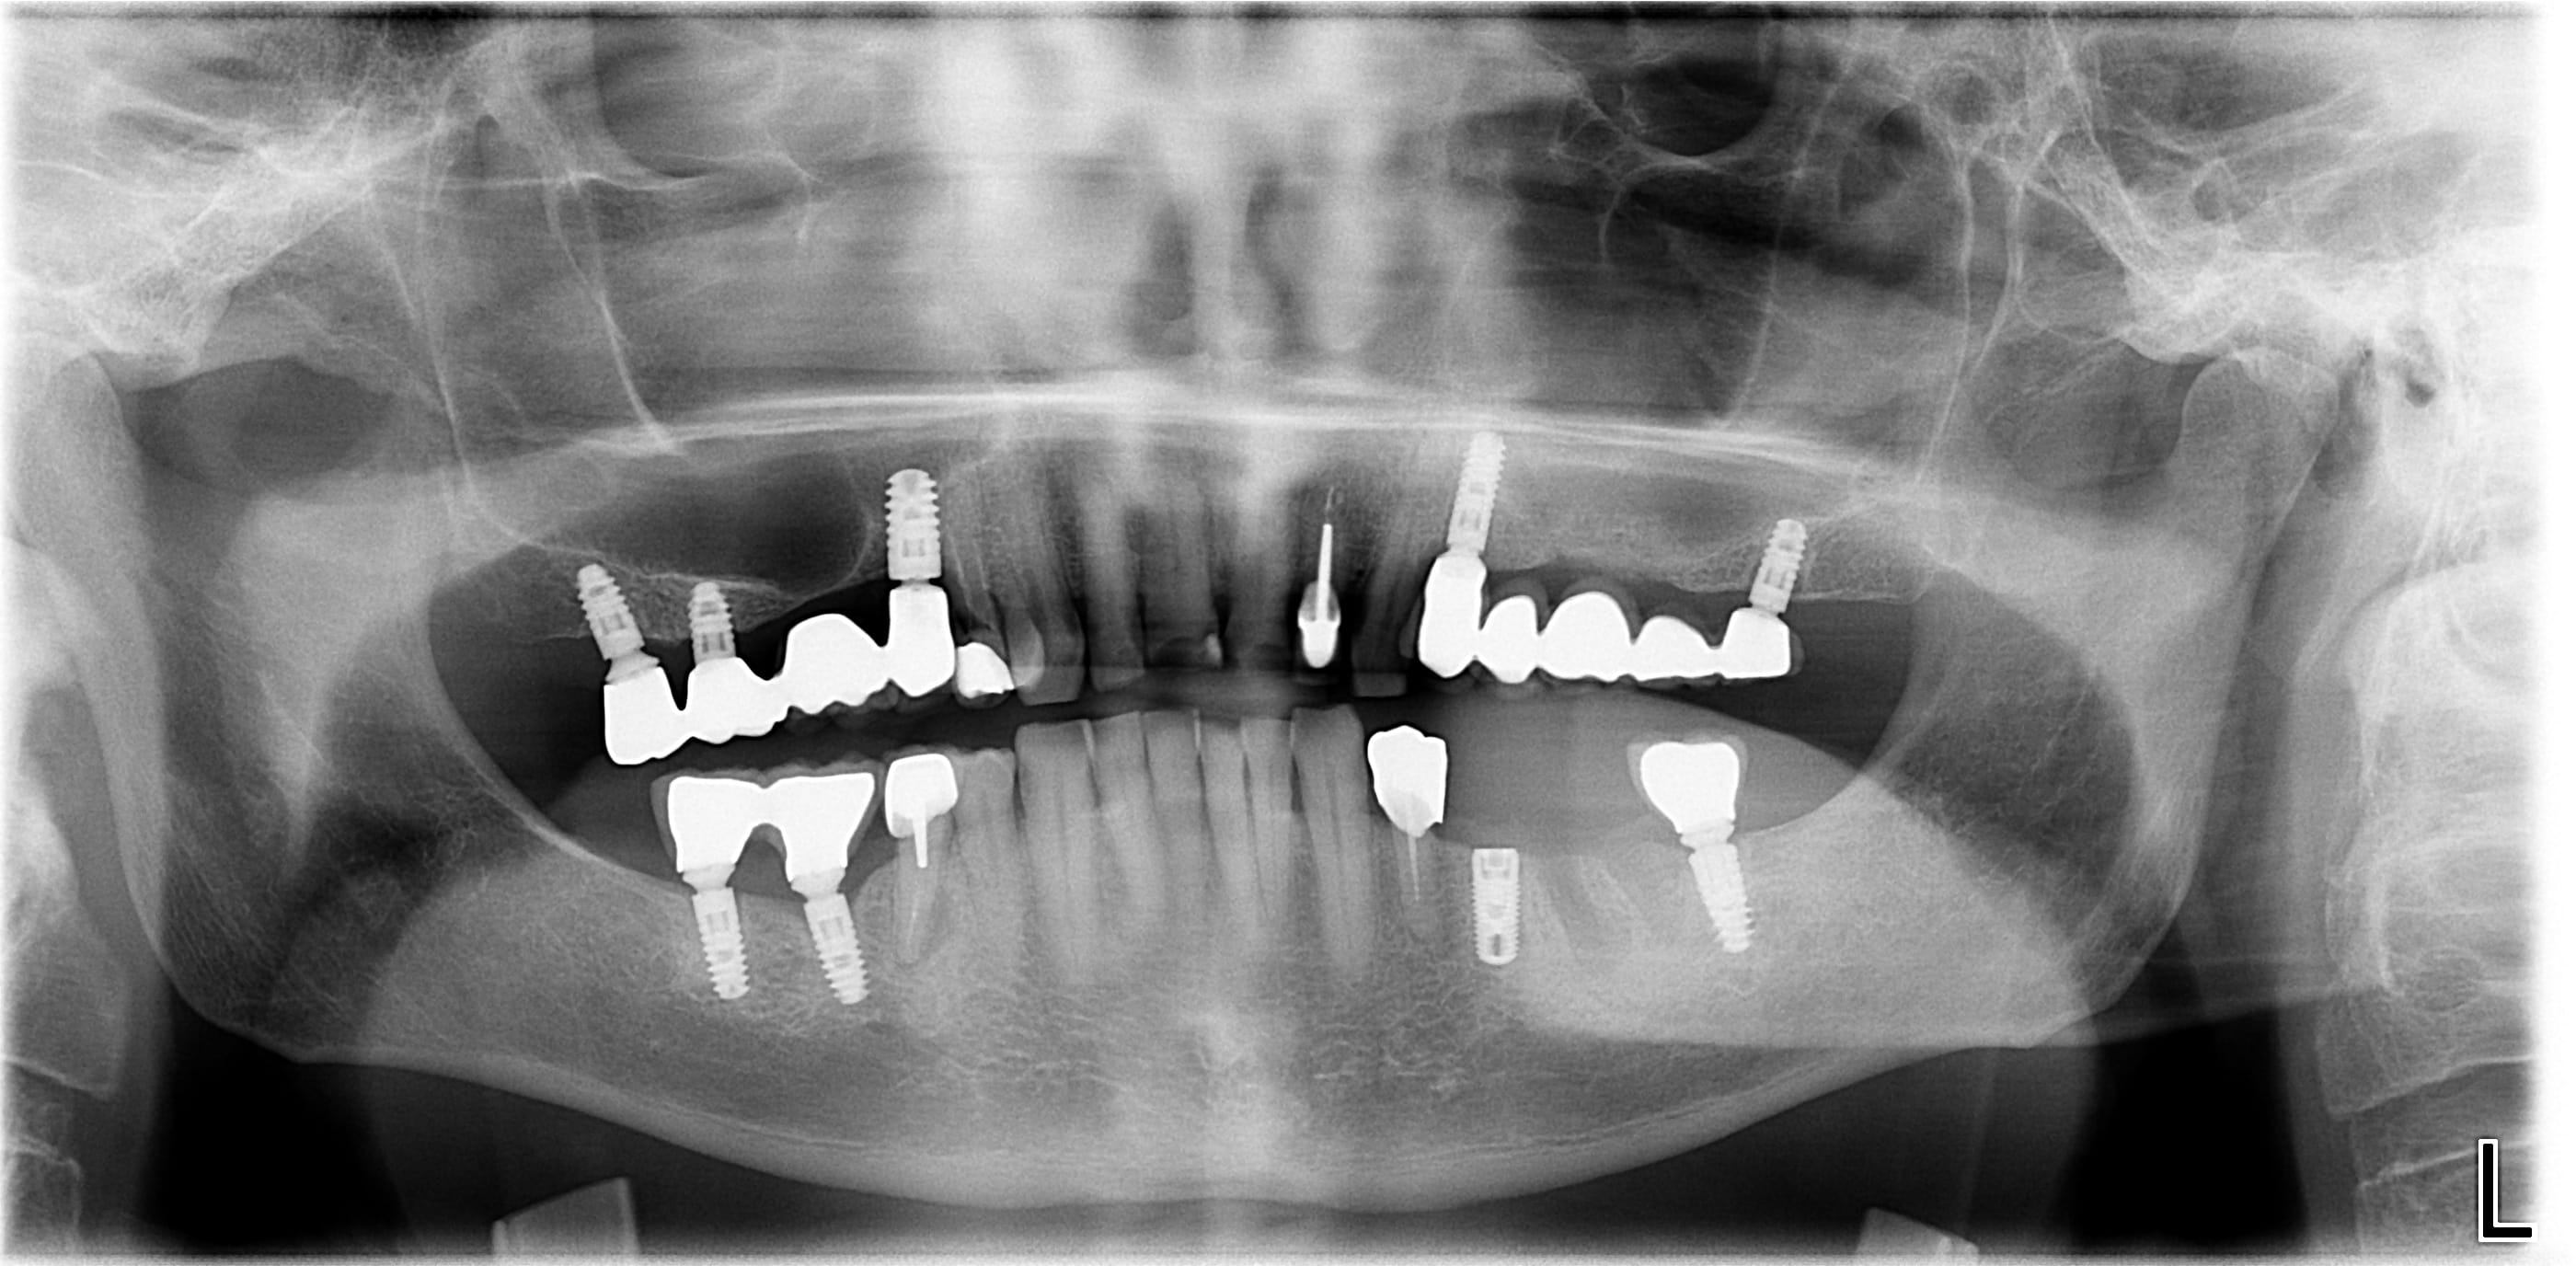

Bonjour, je ne connais pas les implants posés sur ce patient il y a plusieurs années sauf l'implant 35 qui est un zimmer. Le praticien est a la retraite et pas de moyen de savoir ce qu'il posait... Ce qui m’intéresse surtout c'est l'implant 37 pour faire un éventuel bridge 35-37.

rétroalvéolaire pour être sûr à 100% stp...

mais çà a une bonne gueule d'Ankylos....

La seule R.A des implants que j'ai pour le moment pique un peu les yeux...

ouaip, c'est bien de l'ankylos...

normalement la plateforme est restée la même, contacte quand même leur commercial...on ne sais jamais...

il me semble (de mémoire) qu'au début les piliers étaient tous sans indexation...